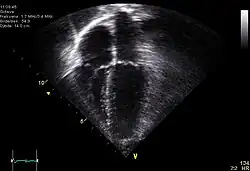

Ecocardiografía

Se utiliza para crear imágenes del corazón que son más detalladas que las imágenes obtenidas por una radiografía simple. Se pueden obtener imágenes en tiempo real en dos o tres dimensiones. Permite evaluar el funcionamiento de las válvulas cardíacas, para el diagnóstico de estenosis o insuficiencia, y para evaluar la contracción del músculo cardíaco, para el diagnóstico de hipertrofia o dilatación de los ventrículos y aurículas.

Se puede hacer una ecocardiografía de esfuerzo para comprobar el funcionamiento del miocardio para bombear la sangre al cuerpo. Se utiliza para detectar una disminución en el flujo sanguíneo al corazón, producido por un estrechamiento de las arterias coronarias.[17]

- Modo M (movimiento): Esta configuración es utilizada para analizar el movimiento de las estructuras del cuerpo de forma cualitativa y cuantitativa, como en el caso de las valvulas del corazón. Es un modo híbrido entre A y B, ya que el brillo de cada línea es modulado a la amplitud de los ecos como en el modo B, pero los ecos son recogidos en una sola dirección, a lo largo del recorrido del rayo como en el modo A.[22]